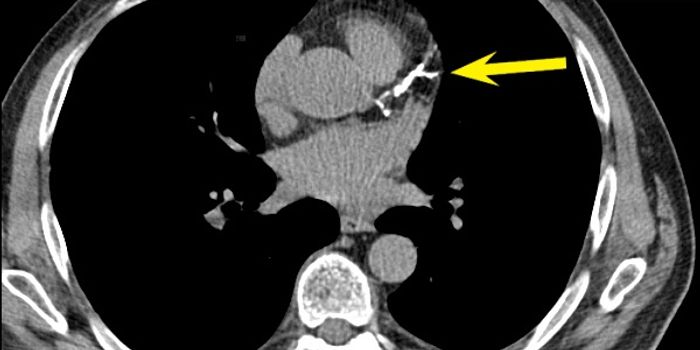

Cardiology is an ever-evolving branch of medicine concerned with disease and disorders of the heart. Cardiology trending provides articles and resources to keep you informed on risk factors, causes and prevention of heart disease, evidence-based research and advances in treatment.